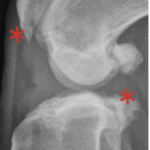

With time, arthritis sets in. Arthritic change includes new bone formation around the joint, called osteophytosis (asterisks).

The knee on the left has a patellar luxation. The knee on the right is normal.